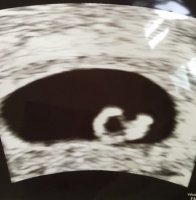

Nååå friker jeg ut. Booket ultralyd dagen jeg blir 8uker, og fikk beskjed om at det gjøres utvendig! Har lest og fått inntrykk av at så tidlig gjøres det innvendig. Men hun har holdt på lenge, så satser på hva hun vet hva hun gjør.

Har noen her tatt utvendig så tidlig? Hva om hun ikke ser det bra nok, kan hun da ta innvendig eller må jeg bestille ny time?

Men fikk faktisk bedre bilder etter at blæren var tømt.